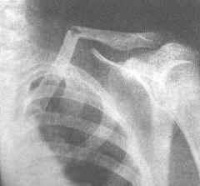

锁骨骨折CT影像图

该病的辅助检查方法主要是影象学检查,锁骨骨折常发生在中段。多为横断或斜行骨折,内侧断端因受胸锁乳突肌的牵拉常向上后移位,外侧端受上肢的重力作用向内、下移位,形成凸面向上的成角、错位缩短畸形。

1、X线检查:X线检查虽较常用,但其误诊率较高,因此在检查时,不能满足于X线正位片未见骨折而诊断为软组织损伤,需仔细检查是否有锁骨内端或对局部骨折征象,以便给予正确的诊断。

2、CT检查:CT检查是目前确定该骨折的最好的辅助检查手段。能清楚地显示骨折的部位和程度,尤其对关节面的骨折优于X线检查。